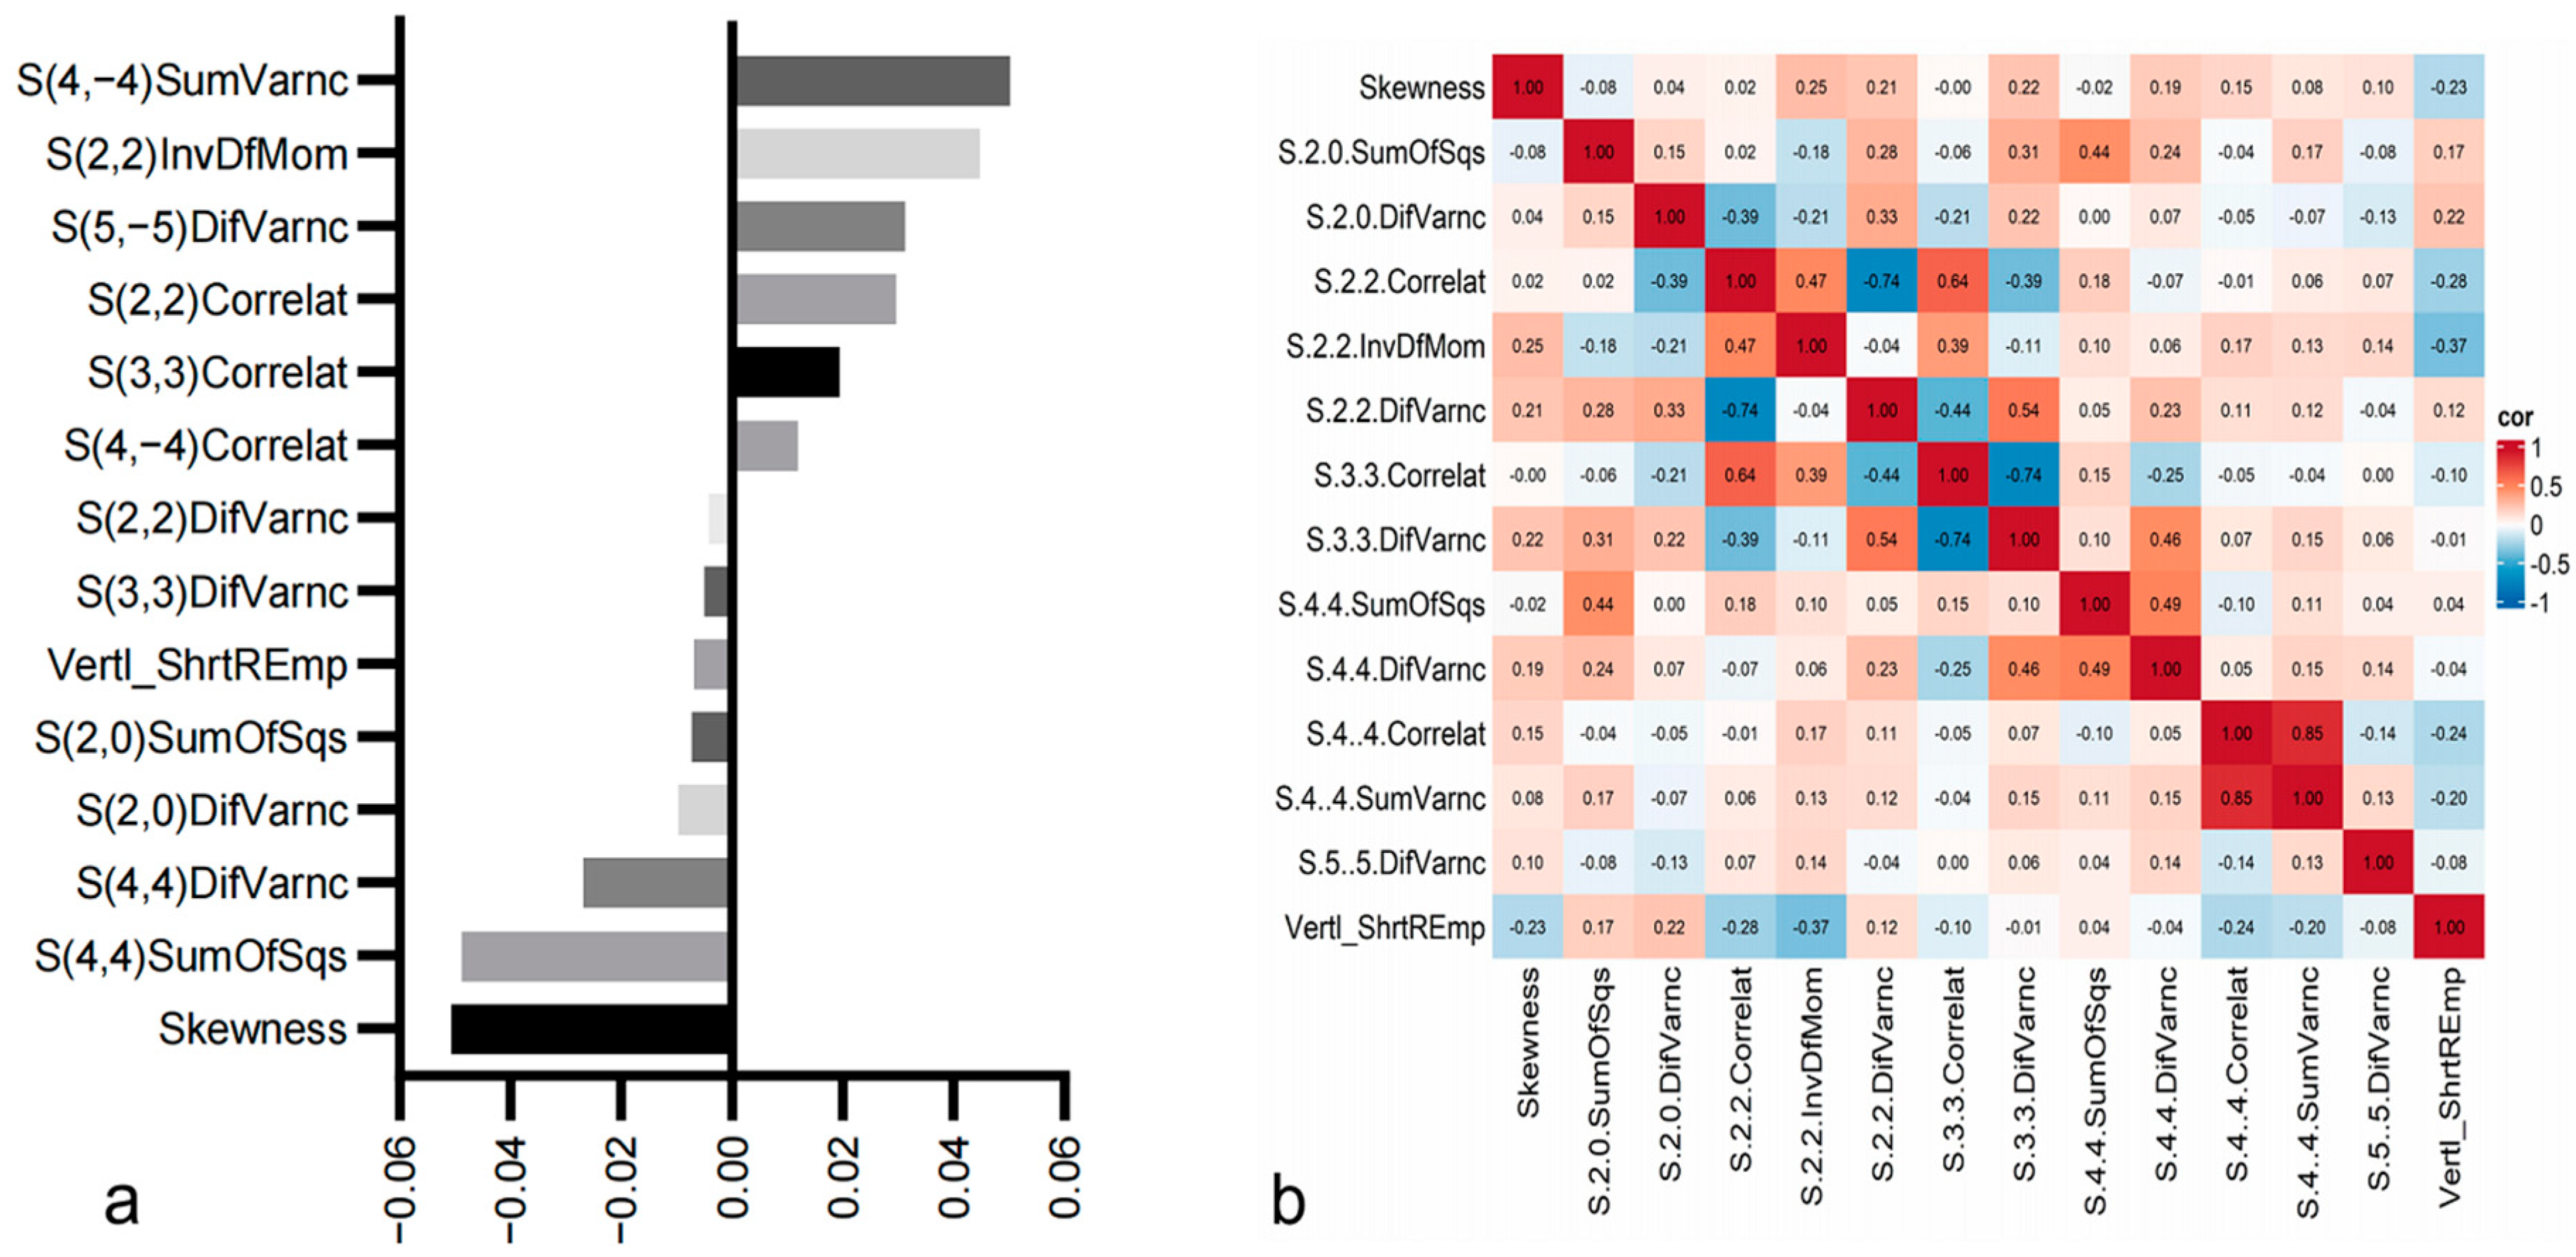

3.2. Radiomics Feature Analysis